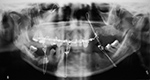

Dental and facial apparatus often is present on cervical spine radiographs and should be evaluated as best as possible even though its evaluation was not the original intent of the imaging study. It is not all that uncommon for important maxillary, mandibular, or dental disease to be incidentally noted on routine imaging of the head, neck, or cervical spine.

Mandibular and maxillary wiring |

The mandibular and maxillary wires were placed to treat the bilateral mandibular fractures. |